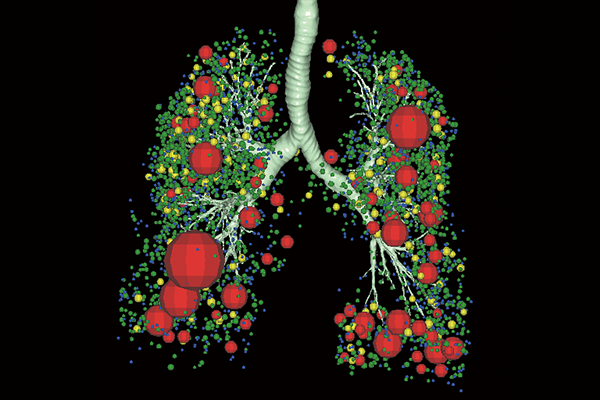

SYNAPSE 3D’s advanced image analysis technology aids clinical interpretation, reporting, and treatment planning. Especially,

automatic organ segmentation technology enables fast and effective workflow, powered by REiLI, FUJIFILM's AI brand. With

a series of high-tech applications developed in collaboration with clinical specialists, SYNAPSE 3D quickly and accurately

delivers imaging result that promotes effective care collaboration.

REiLI makes it happen to extract organs and simplify your work.

Lung lobe

Lung Analysis